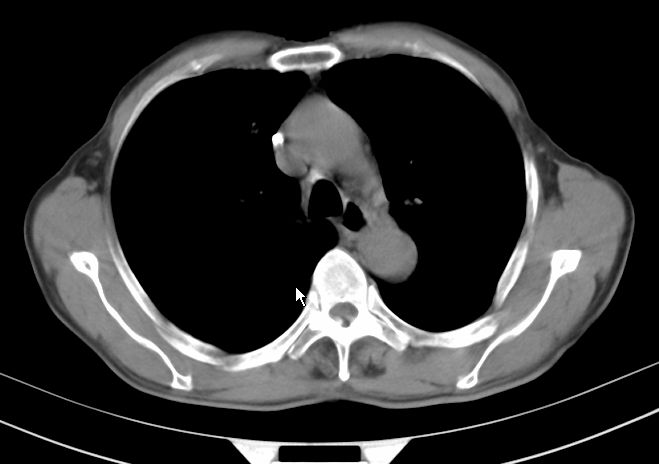

请大家看看是什么性质的。炎性病变首先考虑哪一种炎症。

支持右肺上叶前段\\下叶内基底段感染,建议抗炎治疗后复查,除外结核.

支持右肺上叶前段\\下叶上段感染,建议抗炎治疗后复查,除外结核.

支持右肺上叶前段、下叶内基底段感染,建议抗炎治疗后复查,除外结核.

右肺上叶前段及下叶内基底段感染性病变;建议抗炎治疗后复查。

楼主说是炎症,凭啥?典型的周围型肺癌(腺癌可能性大),肝内可能已有转移,强化看看吧。